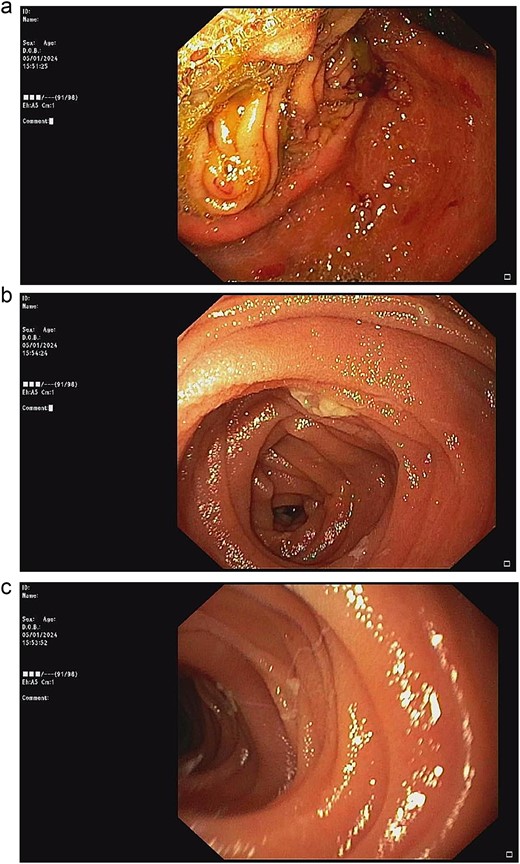

According to these clinical and radiological finding, concern of recurrent gastric outlet obstruction has been raised. Therefore, the computed tomography (CT) scan of the abdomen was performed and showed gastric and afferent limb dilatation, no oral contrast filling in efferent limb and collapsed remaining small bowel loop just distal to gastrojejunostomy anastomosis (Fig. 1). The CT scan findings was afferent limb syndrome associated with efferent limb obstruction due to gastrojejunostomy anastomosis angulation and kinking. The patient was rehydrated with intravenous fluid. Nasogastric tube was placed for decompression. After 5 days of conservative treatment, the abdominal distention was improved but the content from nasogastric tube was continuingly 800–1000 ml per day. Upper endoscopy under general anesthesia was performed for definite diagnosis and chance for endoscopic treatment. It showed patent gastrojejunostomy anastomosis but the both proximal afferent and efferent limb were angulated. Endoscopic dekinking was performed by gentle passage of the endoscope tip across the angulated segment until the intraluminal intestinal segment distal to the obstruction point was reached (Fig. 2).

Upper endoscopic findings: (a) patent gastrojejunostomy anastomosis, (b) afferent limb distal to the angulation, (c) efferent limb distal to the angulation.